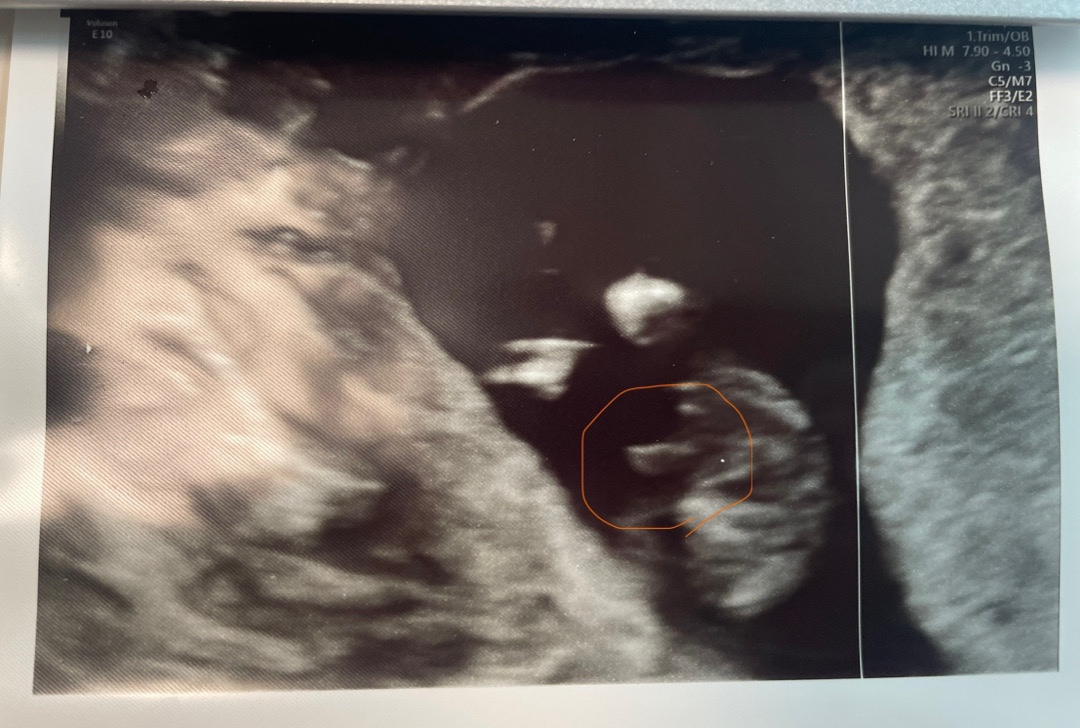

다리 사이에 뭐가 보이는 거 같은데… 같이 봐주세요!

주황색 실선 동그라미에요 주차는 13주 2일이고 아이 크기는 14주인데 아들일까요? 🫢 오늘 니프티도 같이 하고 와서 다음 주면 확실하게 알긴 할텐데도 너무 궁금해요 ㅋㅋ